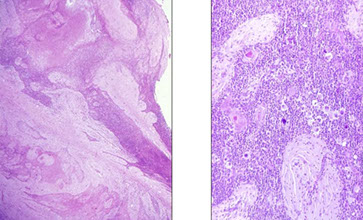

- Nodular sclerosis classic Hodgkin lymphoma